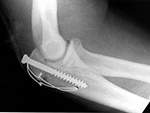

Tension band wire |

Tension band fixation of an olecranon fracture using a cancellous screw. The looped wire transforms the distractive pull of the triceps into compression at the fracture site. From Benjamin, 1994 |